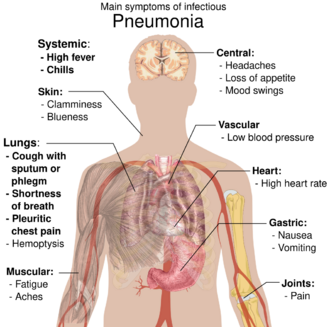

People with infectious pneumonia often have a productive cough, fever accompanied by shaking chills, shortness of breath, sharp or stabbing chest pain during deep breaths, and an increased rate of breathing.[9] In elderly people, confusion may be the most prominent sign.[9]

The typical signs and symptoms in children under five are fever, cough, and fast or difficult breathing.[23] Fever is not very specific, as it occurs in many other common illnesses and may be absent in those with severe disease, malnutrition or in the elderly. In addition, a cough is frequently absent in children less than 2 months old.[23] More severe signs and symptoms in children may include blue-tinged skin, unwillingness to drink, convulsions, ongoing vomiting, extremes of temperature, or a decreased level of consciousness.[23][24]

Bacterial and viral cases of pneumonia usually result in similar symptoms.[25] Some causes are associated with classic, but non-specific, clinical characteristics. Pneumonia caused by Legionella may occur with abdominal pain, diarrhea, or confusion.[26] Pneumonia caused by Streptococcus pneumoniae is associated with rusty colored sputum.[27] Pneumonia caused by Klebsiella may have bloody sputum often described as "currant jelly".[22] Bloody sputum (known as hemoptysis) may also occur with tuberculosis, Gram-negative pneumonia, lung abscesses and more commonly acute bronchitis.[24] Pneumonia caused by Mycoplasma pneumoniae may occur in association with swelling of the lymph nodes in the neck, joint pain, or a middle ear infection.[24] Viral pneumonia presents more commonly with wheezing than bacterial pneumonia.[25] Pneumonia was historically divided into "typical" and "atypical" based on the belief that the presentation predicted the underlying cause.[28] However, evidence has not supported this distinction, therefore it is no longer emphasized.[28]